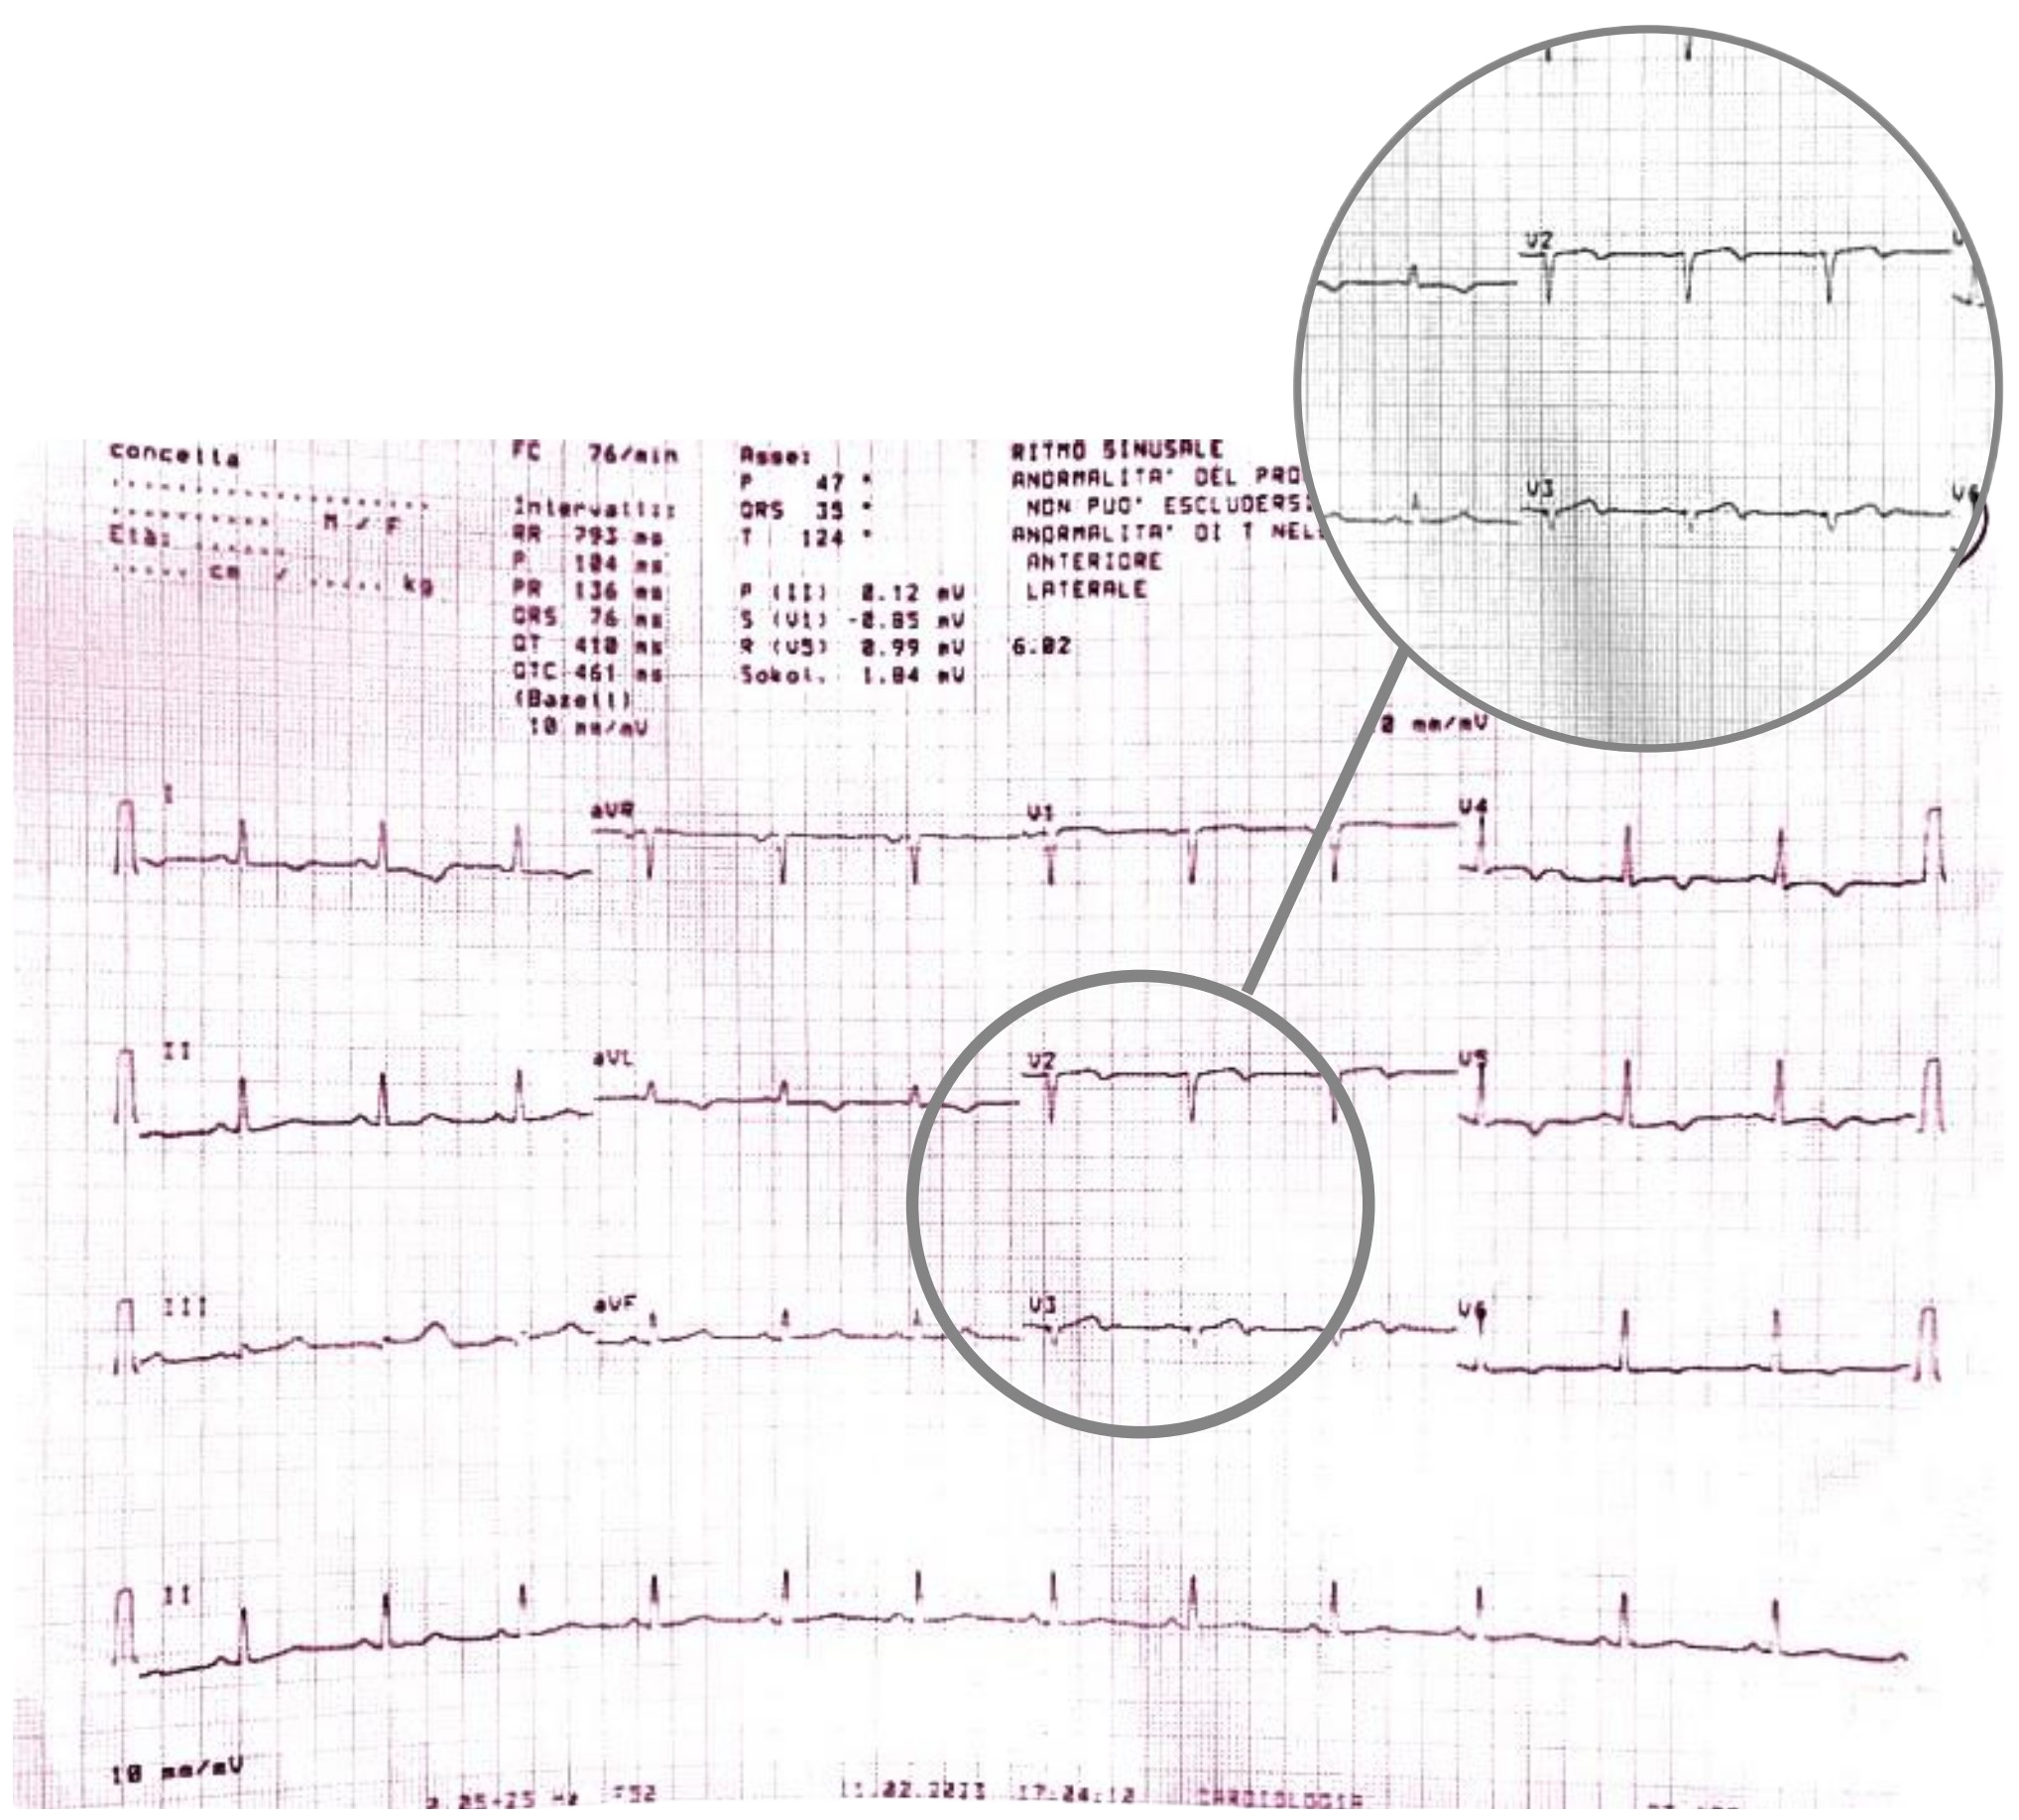

During the hospitalization, the patient experienced the recurrence of similar episodes of mild chest pain; all of them occurred after minor exertion, lasted a few minutes and were self-resolving. The 12 leads ECG performed during the last one of them showed few changes: biphasic T waves with initial positivity and terminal negativity in leads V2 and V3 slightly resembling type A Wellens pattern were present (Fig. 4 — ECG).

Fig. 4.

Fig. 4.ECG showing biphasic T waves with initial positivity and terminal negativity in leads V2 and V3 slightly resembling type A Wellens Syndrome. ECG, electrocardiogram.